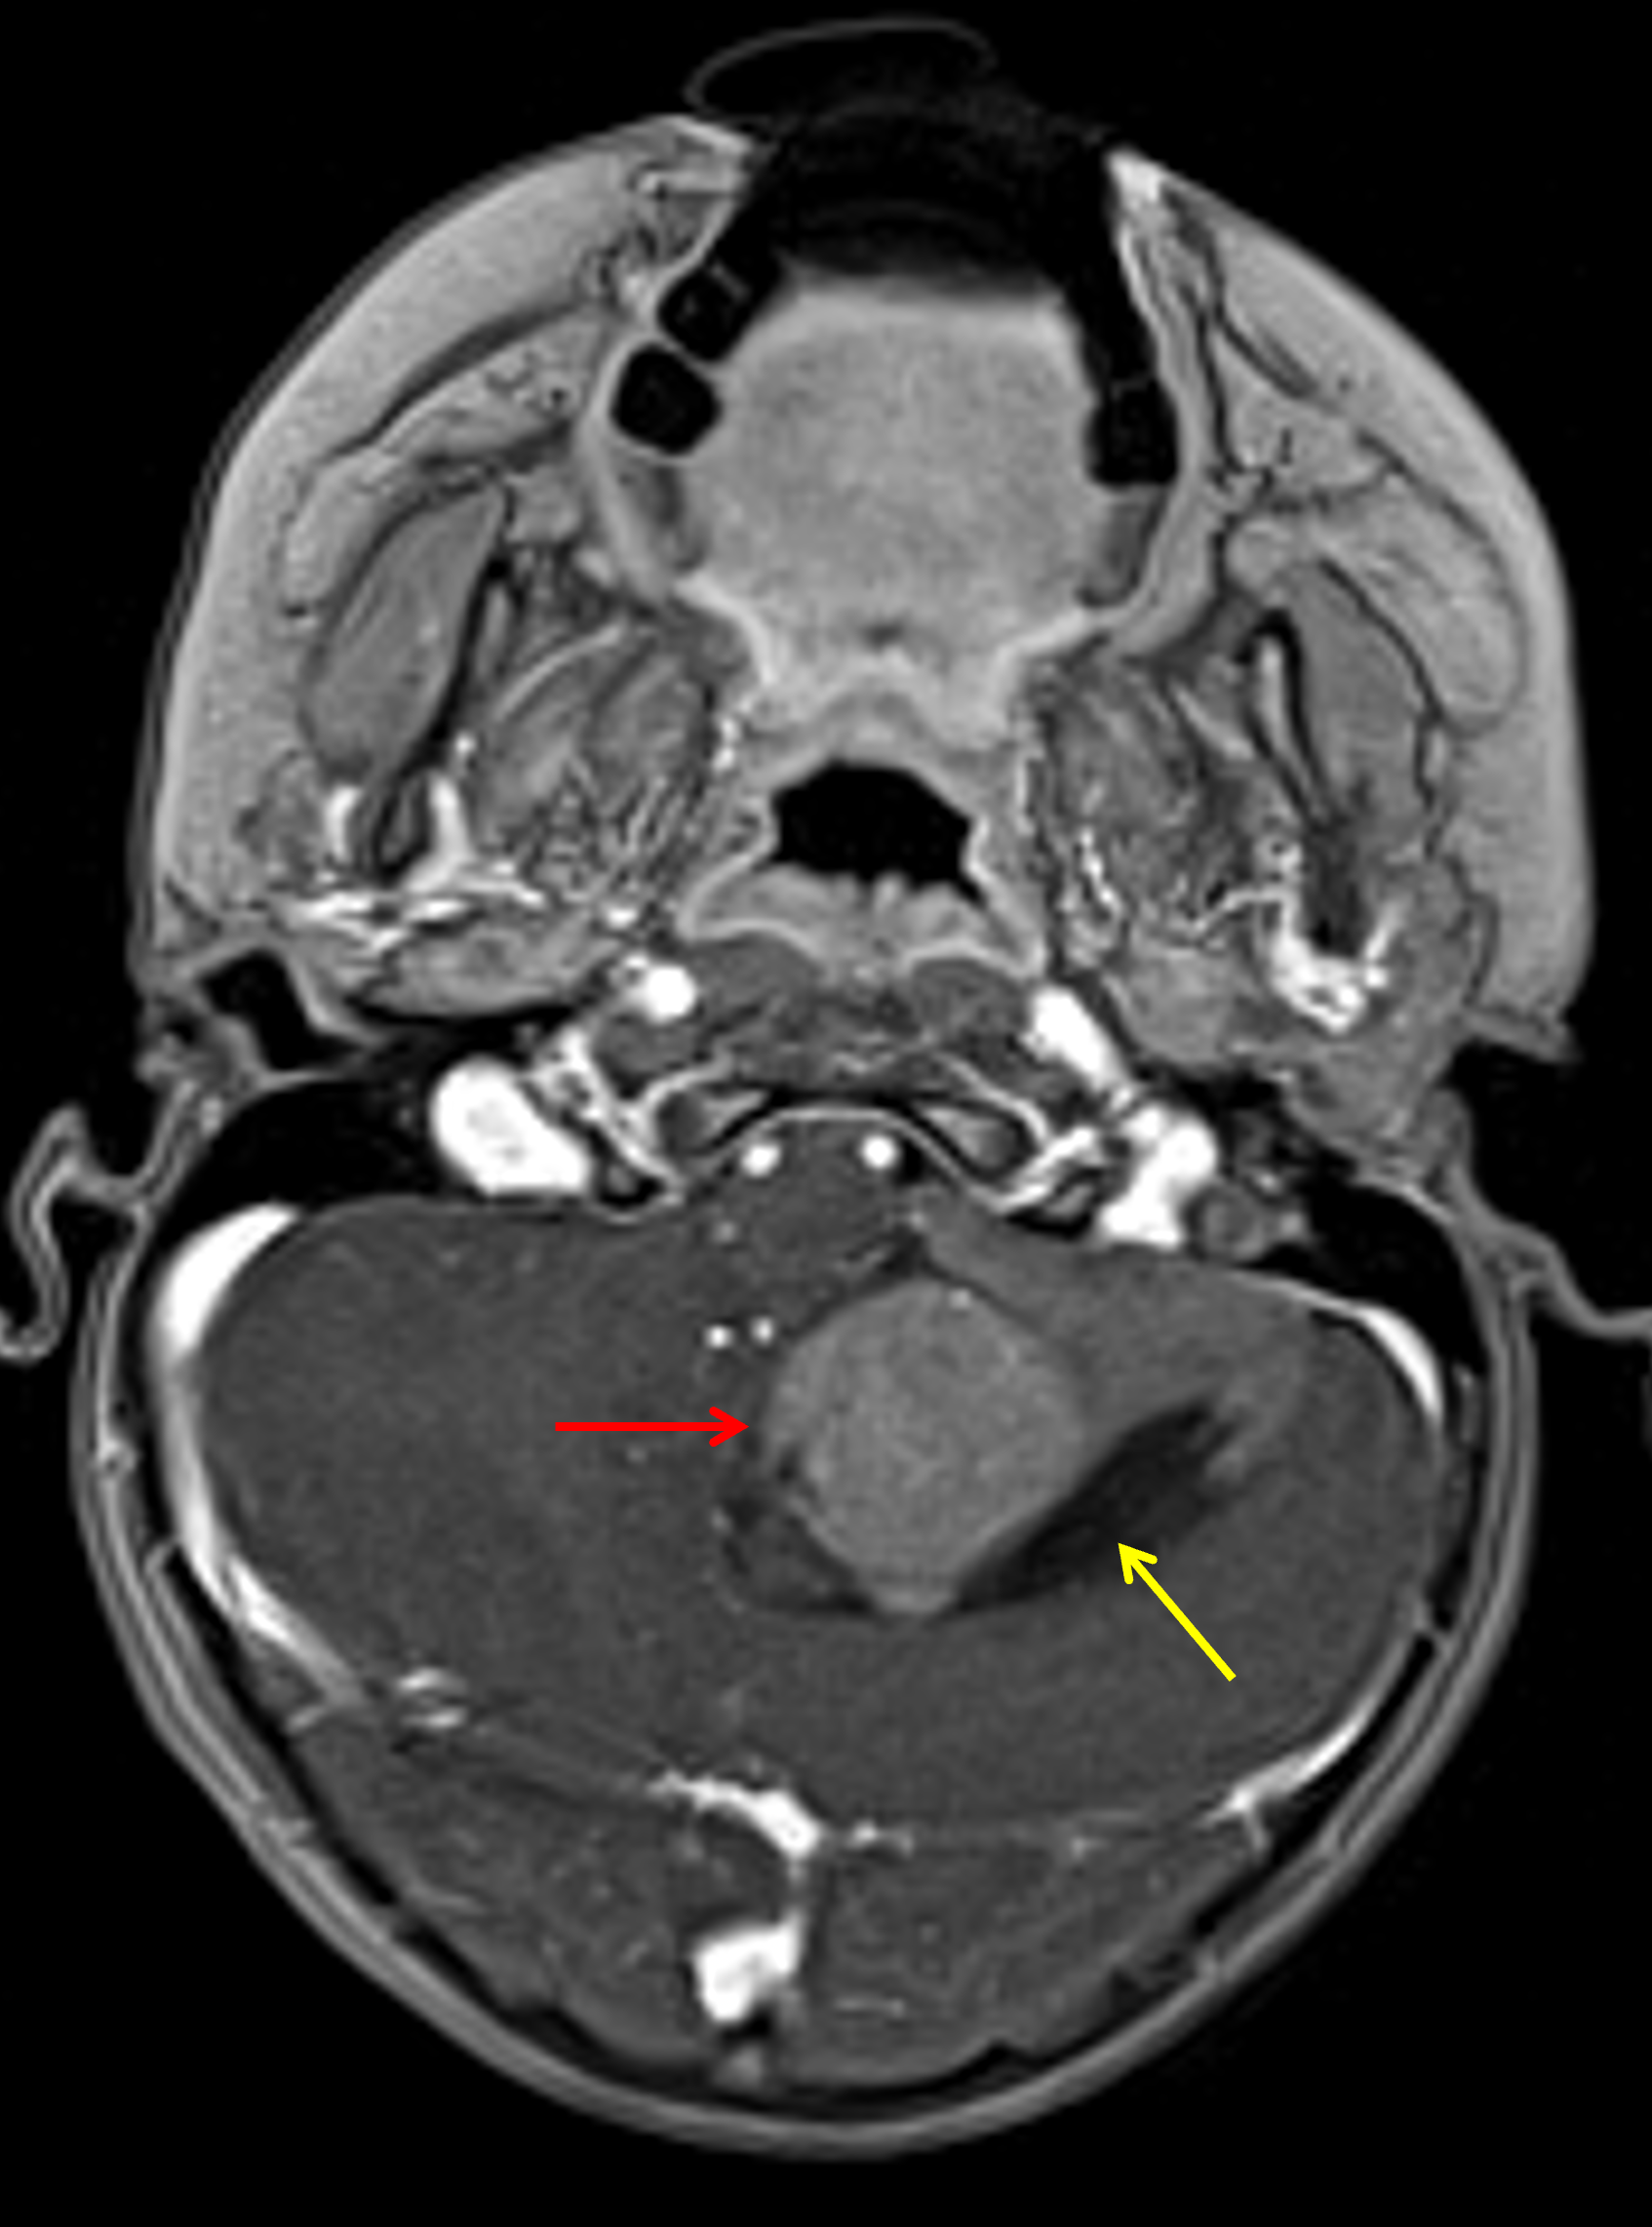

Age: 3

Sex: Female

Indication: Gait instability, confusion

CT

Medulloblastoma (SHH-activated, TP53 wild-type, nodular desmoplastic histology)